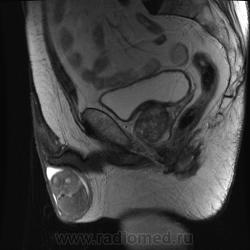

"Мужчина, 60 лет. Около 3 месяцев назад появился дискомфорт в области мошонки, увеличение правого яичка."

Считаю, что семинома - не самый вероятный вариант, т.к. структура опухоли достаточно неоднородная, есть распространение на придаток и границы четкие.

Могу предположить, неоплазию правого яичка.

Я в заключении вынес на первый ряд карциному яичка.